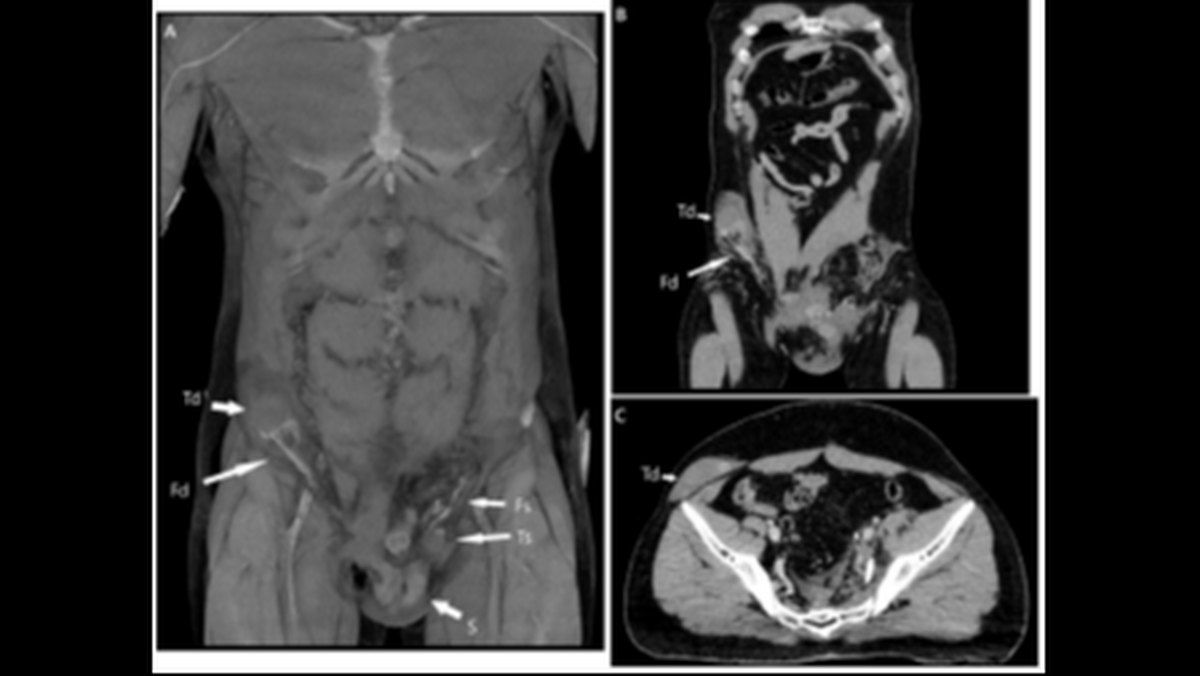

On the right side of the man’s body, lodged in the upper portion of the pelvis past the bladder, was his other testicle, fully intact, according to the report.

The man’s testicle, marked by the letters “Td,” moved to the upper right portion of his pelvis, doctors said.

The man’s testicle, marked by the letters “Td,” moved to the upper right portion of his pelvis, doctors said. BMJ Case Reports 2023